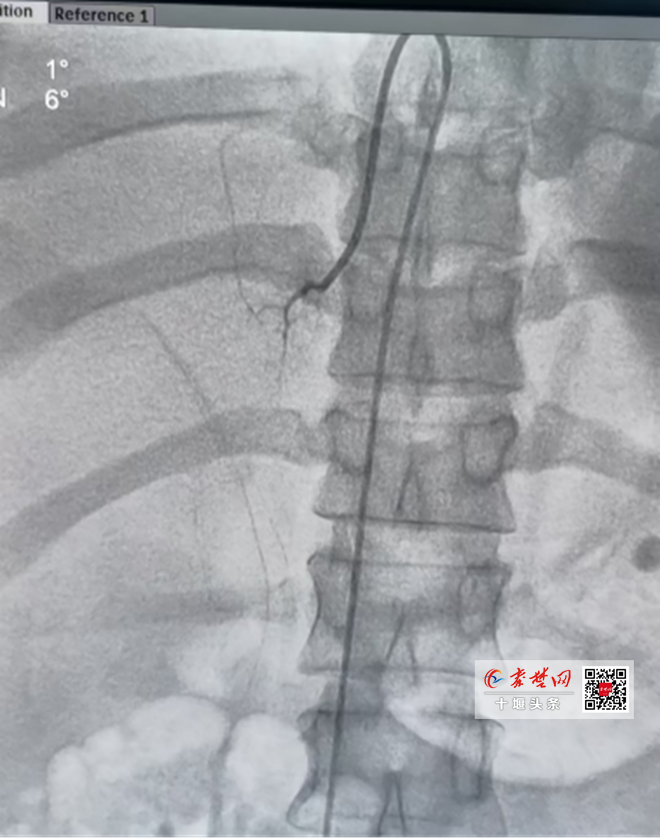

據(jù)趙繼先主任介紹,該技術(shù)采用微創(chuàng)介入技術(shù),通過股靜脈,對患者雙側(cè)腎上腺中心靜脈分段采血,更能直接、準(zhǔn)確測定醛固酮、腎素等腎上腺激素局部水平。但在介入過程中,由于腎上腺靜脈較為細(xì)小、解剖變異多,難度大,對操作者的介入技術(shù)要求相當(dāng)高,并且需要非常豐富的介入手術(shù)技巧才能完成。

手術(shù)由沈俊博士、夏南博士、曾海星主治醫(yī)師組成介入團(tuán)隊(duì)成功實(shí)施,過程順利。術(shù)后ARR證實(shí)患者為原發(fā)性醛固酮增多癥,患者雖然雙側(cè)腎上腺有結(jié)節(jié),但是左側(cè)腎上腺醛固酮分泌為右側(cè)80倍,左側(cè)腎上腺為醛固酮分泌優(yōu)勢側(cè)。下一步,手術(shù)團(tuán)隊(duì)擬對患者左側(cè)腎上腺結(jié)節(jié)采取微創(chuàng)手術(shù)。

沈俊博士介紹,腎上腺靜脈取血術(shù)(AVS)是一種微創(chuàng)的介入檢查手段,是原發(fā)性醛固酮增多癥定位診斷的 “金標(biāo)準(zhǔn)”。它不僅能夠精準(zhǔn)判斷患者是否有醛固酮增多癥,還能精確診斷哪一側(cè)腎上腺是優(yōu)勢分泌側(cè),為精準(zhǔn)治療以及后續(xù)手術(shù)的精準(zhǔn)定位提供保障,有效避免誤切非優(yōu)勢側(cè)腎上腺,確保手術(shù)質(zhì)量。接受 AVS 指導(dǎo)下的腎上腺手術(shù)的患者,高血壓有望治愈,從而擺脫終身服藥的困擾。